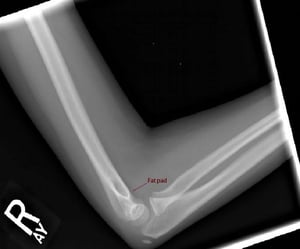

Radiografia del gomito

Radiografia di profilo del gomito

La linea omerale anteriore e la linea radiocapitellare sono normali. Tuttavia, è presente un cuscinetto adiposo anteriore, che suggerisce un versamento articolare.

La linea omerale anteriore e la linea radiocapitellare sono normali. Tuttavia, è presente un cuscinetto adiposo anterio

Image courtesy of Danielle Campagne, MD.